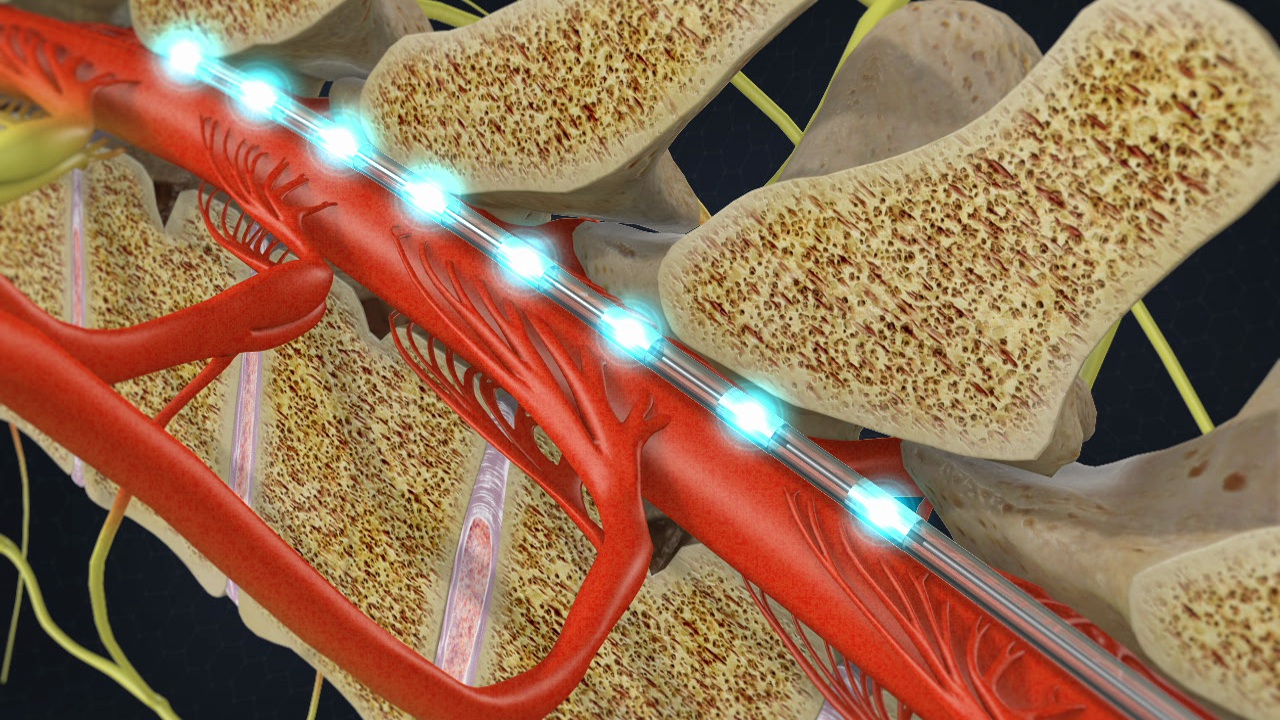

Spinal Cord Stimulators Market Achieves Electrifying Milestone, Surpassing US$ 5.3 Billion in 2032

The spinal cord stimulators market has grown significantly in recent years as a result of the rising incidence of chronic pain conditions and the rising demand for non-pharmaceutical pain management techniques. Medical devices known as spinal cord stimulators (SCS) are used to treat conditions like failed back surgery syndrome, complex regional pain syndrome, and neuropathic …